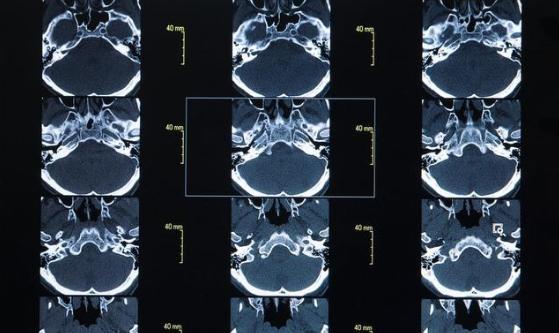

医生立即对男孩进行体征检查,判断可能是脑部血管出现了问题,同时抽血检查血液。医生申请急诊绿色通道进行脑部CT检查,发现大脑内一血管已严重堵塞。